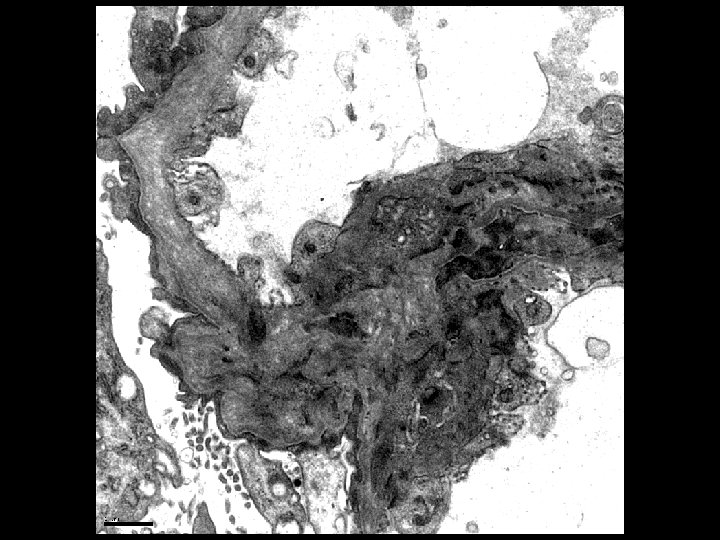

Electron Microscopy • Lamellation, thickening and thinning of GBMs

Alport’s Syndrome • Recurrent hematuria • Nerve deafness • Usually presents in early 20’s • Classic renal biopsy features by EM – Thickened and Thinned GBM – Lamination and Rarefaction – Grains